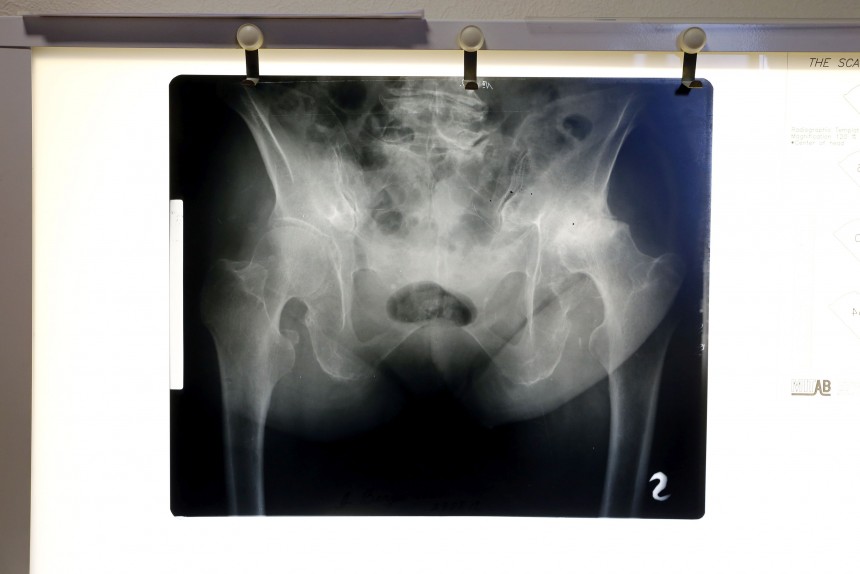

Mediķi turpina kurnēt par atalgojumu: vai nebūs kas taisa rentgenu?

Veselības ministrija apgalvo, ka plānotās izmaiņas radioloģijas tarifa pārskatīšanā neskars mediķu atalgojumu, proti, tas nesamazināšoties. Pretēji ministrijai Veselības aprūpes un darba devēju asociācijas valdes priekšsēdētājs Māris Rēvalds uzsver, ka tarifu aprēķināšanā ir pieļauta kļūda un tas izraisīs kritisku atalgojuma samazināšanos ārstiem radiologiem un radiologu asistentiem.

Veselības ministrijas speciālists Oskars Šneiders Neatkarīgajai skaidro, ka atbilstoši Ministru kabineta uzdevumam Veselības ministrija sagatavojusi piedāvājumus saistībā ar radioloģijas tarifu pārskatīšanu. Darba grupas ietvaros ir izvērtēts un izstrādāts radioloģijas izmeklējumu apmaksas tarifu projekts, pārskatot iekārtu amortizācijas piemaksas daļu datortomogrāfijas, ultrasonogrāfijas un magnētiskās rezonanses un rentgena iekārtām. «Tarifs bija jāpārskata, izvērtējot finansējuma izlietojumu veselības nozarē un ņemot vērā, ka iekārtām laika gaitā ir ievērojami samazinājušās cenas, lai arī amortizācijas piemaksas līdz šim saglabājušās iepriekšējo aprēķinu līmenī,» saka O. Šneiders. Izstrādātajā radioloģijas izmeklējumu apmaksas tarifu projektā paredzēts, ka amortizācijas piemaksas daļa tiek noteikta pēc vienotiem principiem, turklāt pārskatīts ir tieši iekārtu amortizācijas izmaksu apjoms, nevis atalgojuma sadaļa - tā nemainīsies.